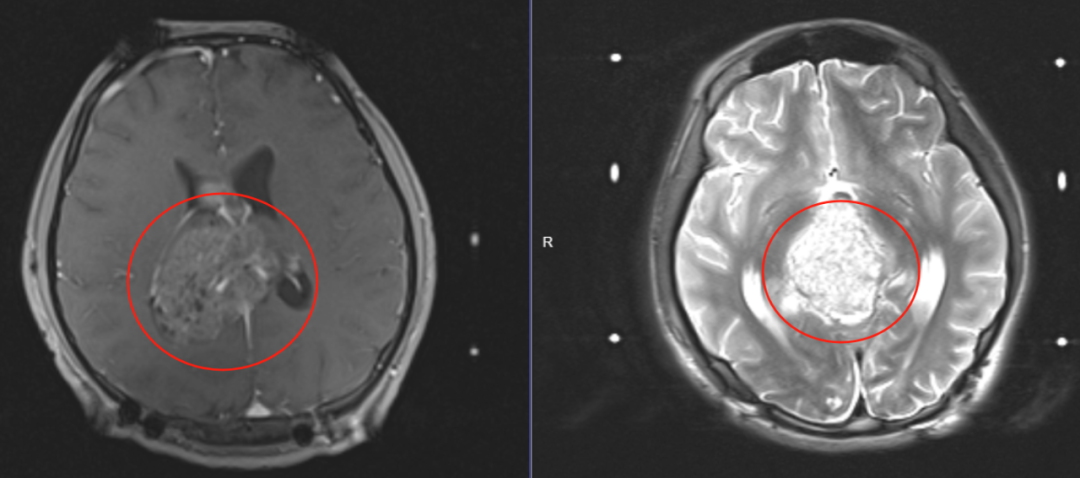

(治疗前2023年10月影像资料)

(治疗后2024年2月复查 影像资料 显示肿瘤消失 )